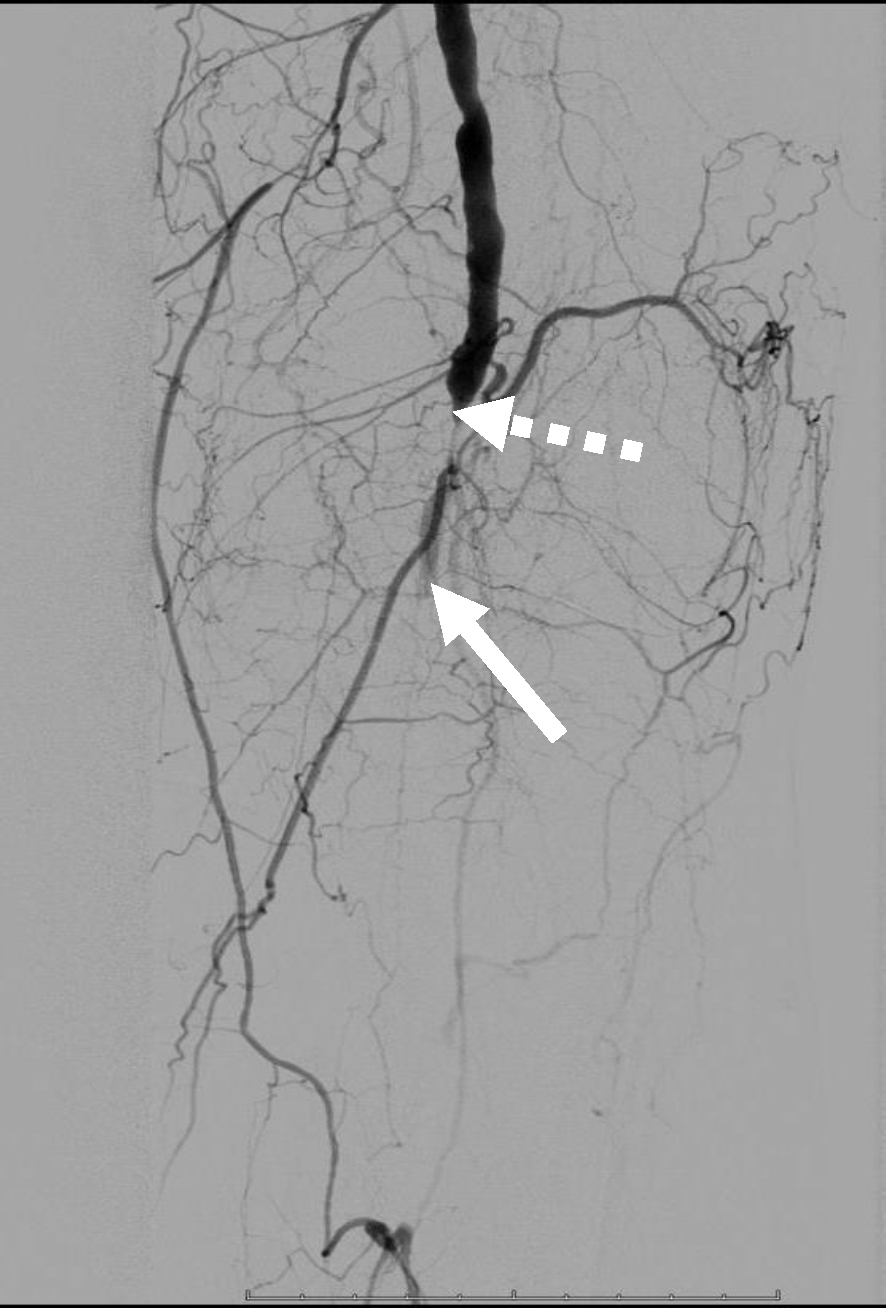

Операция. Транслюминальная баллонная ангиопластика (ТЛБАП) подколенной артерии, тибиоперонеального ствола слева. Под м/а выполнена пункция левой бедренной артерии, установлен интродьюсер 6 Fr. Выполнена селективная ангиграфия артерий левой нижней конечности при которой выявлена субокклюзия подколенной артерии и окклюзия тибиоперонеального ствола (рис. 1). Выполнена ТЛБАП в зоне субокклюзии баллоном 5,0 × 40 мм, давление 8 атм. В области тибиоперонеального ствола ТДБАП баллоном 3,0 мм × 100 мм, давление 10 атм. Получен хороший антеградный кровоток в подколенной, заднебольшеберцовой и малоберцовой артериях (рис. 2). Передняя большеберцовая артерия окклюзирована.

Рис. 1. Ангиограмма больной М. до ангиопластики. Стеноз подколенной артерии (прерывистая стрелка). Окклюзия артерий голени (сплошная стрелка)

Рис. 2. Ангиограмма больной М. после ангиопластики. Восстановление магистрального кровотока в проксимальном (а) и дистальном (б) отделах голени